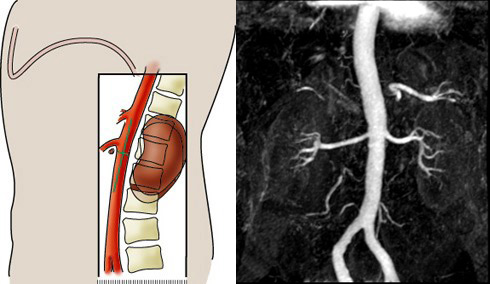

MR Renal Arterial Stenosis protocol - Scanning for Coronal 3D mDixon

MR Renal Arterial Sclerosis Protocol - Scanning for 3D BTFE